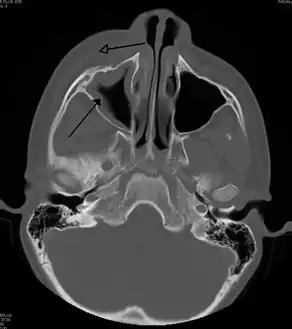

| A CT scan showing sinusitis of the ethmoid sinus | |

For sinusitis lasting more than 12 weeks, a CT scan is recommended.[54] On a CT scan, acute sinus secretions have a radiodensity of 10 to 25 Hounsfield units (HU), but in a more chronic state they become more viscous, with a radiodensity of 30 to 60 HU.[56]

CT of chronic sinusitis

CT scan of chronic sinusitis, showing a filled right maxillary sinus with sclerotic thickened bone.